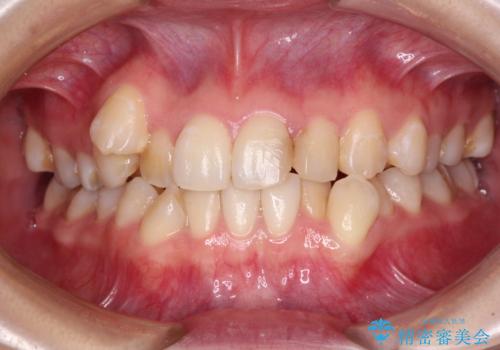

ワイヤー矯正で確実にガタつきを治したい セラミックブラケットによる治療